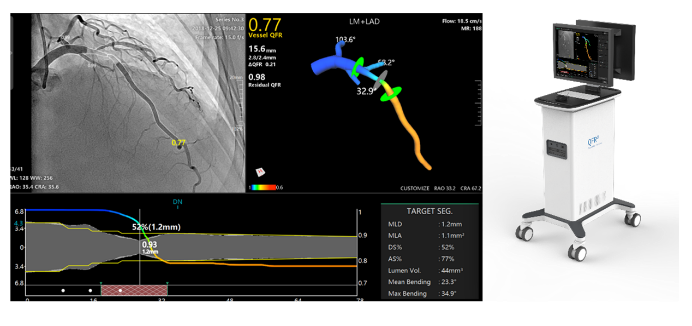

涂圣贤团队研制了一种基于冠脉影像评估血管生理功能的定量血流储备分数检测仪。系统可安装在医院介入导管室,通过网络获取导管室造影机采集的造影影像或血管内成像影像,实现快速冠状动脉三维重建与血流储备分数计算(含QFR、OFR与UFR),用于在线判断重建血管的解剖参数与功能缺血状况,以优化支架植入手术。

QFR界面示意 |